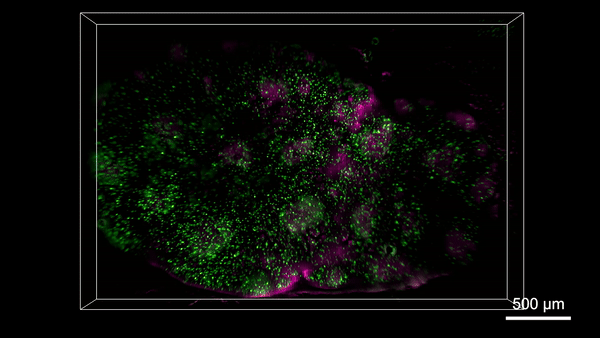

The RUSH3D system provides an unprecedented tool for studying large-scale cell interactions. For example, germinal centers (GCs) are structures formed by the aggregation of antigen-activated B cells under the guidance of chemotaxis. Due to limitations in field of view and recording duration, the process of how immune cells participate in the generation of multiple GCs and migrate between them has never been continuously recorded. The team used RUSH3D to perform high-speed three-dimensional imaging of lymph nodes near the inguinal region of mice during an immune response for over ten hours, spanning approximately 85 hours. This allowed them to completely record the process of B cells participating in the generation of multiple GCs. Simultaneously, they observed the complete migration of some T cells between multiple GCs 145 hours into the immune response, after the GCs had fully formed. This suggests that T cells may be involved in information exchange and transmission between GCs. RUSH3D has achieved, for the first time, continuous in vivo observation of immune responses at the whole-organ scale, particularly the entire process from tumorigenesis to immune response and tumor growth, fully revealing the immune activation response triggered by tumors. RUSH3D's observation of messenger T cells exchanging information between different germinal centers is expected to uncover new immune mechanisms and unveil the mystery of tumor metastasis from a mesoscale in vivo perspective for the first time.

Figure 5. RUSH3D captured multiple germinal centers (GCs) formation

Figure 6. Migration of T cells over multiple germinal centers